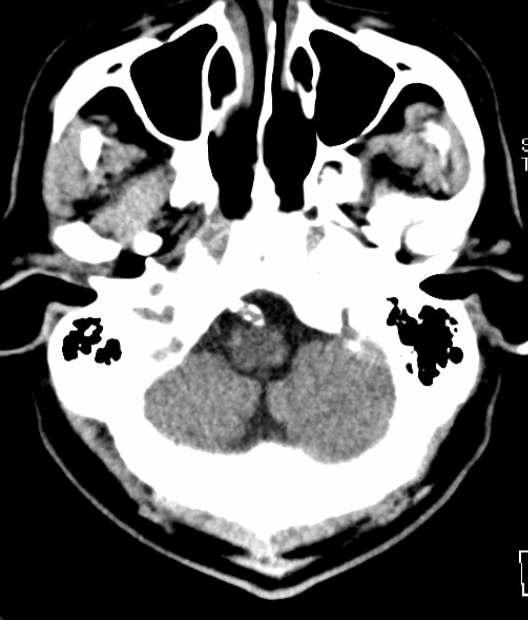

术前MRI+MRA示:脑桥急性梗死,动脉瘤位于基底动脉近端,左侧椎动脉优势。

术后颅脑CT平扫: